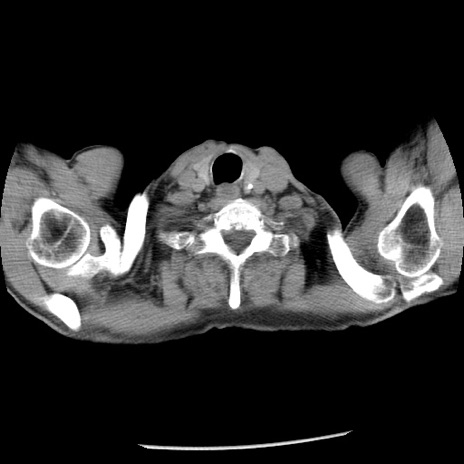

症例26(横断像)

【症例】80歳代男性

【主訴】嘔吐

【現病歴】昨晩2回嘔吐あり、今朝になっても嘔吐あり。来院。

【既往歴】胃潰瘍

【身体所見】意識清明、BT 37.6℃、BP 166/95mmHg、HR 100bpm、SpO2 97%、腹部:平坦・軟、腸蠕動音聴取良好、圧痛なし。

【データ】WBC 21900、CRP 1.46